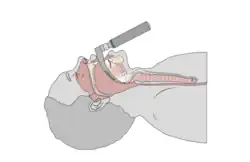

Direct laryngoscopy

Direct laryngoscopy is carried out (usually) with the patient lying on their back; the laryngoscope is inserted into the mouth on the right side and flipped to the left to trap and move the tongue out of the line of sight, and, depending on the type of blade used, inserted either anterior or posterior to the epiglottis and then lifted with an upwards and forward motion ("away from you and towards the roof "). This move makes a view of the glottis possible. This procedure is done in an operation theatre with full preparation for resuscitative measures to deal with respiratory distress. There are at least ten different types of laryngoscope used for this procedure, each of which has a specialized use for the otolaryngologist and medical speech pathologist. This procedure is most often employed by anaesthetists for endotracheal intubation under general anaesthesia, but also in direct diagnostic laryngoscopy with biopsy. It is extremely uncomfortable and is not typically performed on conscious patients, or on patients with an intact gag reflex.